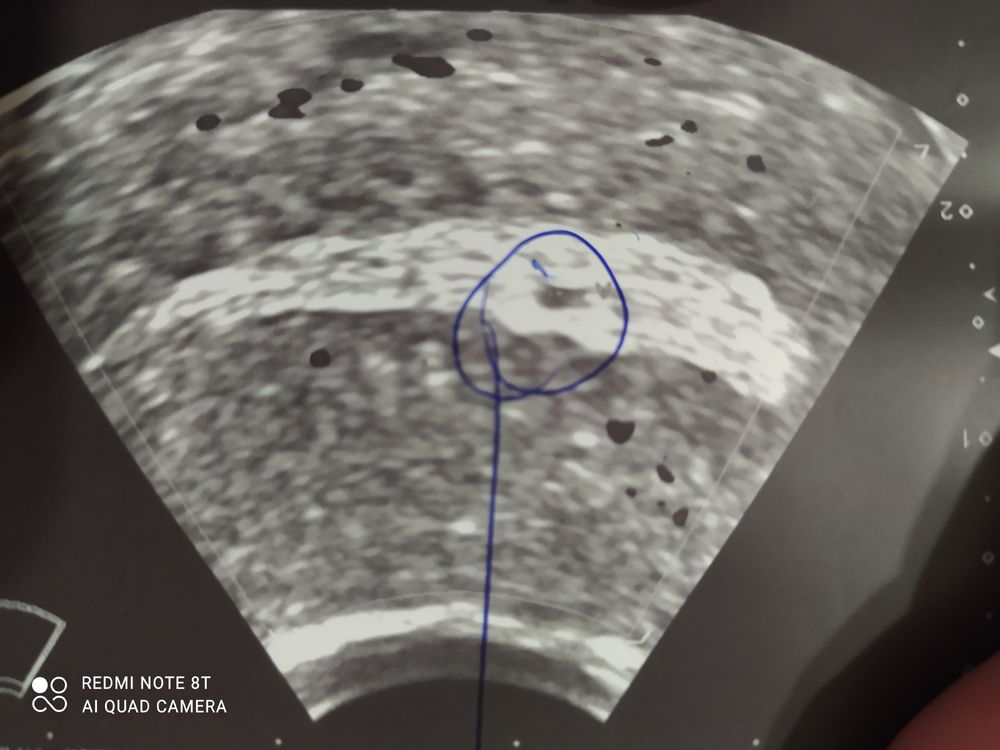

Замершая беременностьЗадержка месячных очень большая, пошла на УЗИ поставили под вопросом плодное яйцо 2мм, сдала ХГЧ 1.20. Как я поняла беременности нет! Тогда что? Может у кого было такое? На УЗИ через 2 недели.

Юлия, УЗИ под вопросом нашли похожее на плодное яйцо, но не факт что оно, кисты нет

Мария Левина, а фото есть? Мне кажется, хгч не врет. Плодное яйцо на узи примерно от 1000 видно… Сколько времени у вас прошло между анализом хгч и узи?